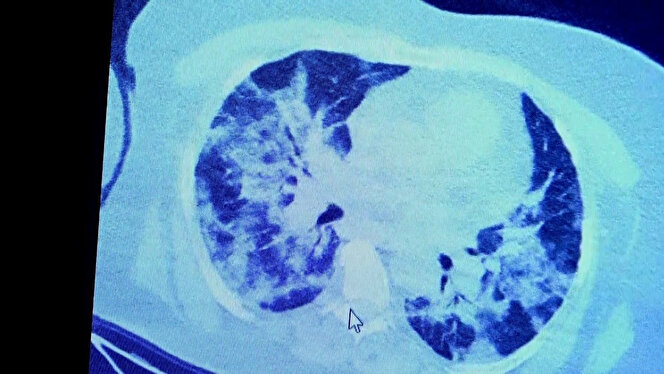

Koronavirüs testi pozitif çıkan hastaların ilaç kullandığı ve kullanmadığı durumda akciğerlerinin hali görüntülendi. Prof. Dr. Şevket Özkaya, bir hafta ilaç kullanmayan bir pozitif hastanın akciğer tomografisini inceledi. Hasta pozitif haldeyken ilk akciğer tomografisine bakıldı. Tomografide akciğerlerdeki tutulmanın az olduğu gözlemlendi. Sonra da aynı hastanın verilen ilaçları kullanmamış ve 1 hafta boyunca tedaviye uymamış haldeki akciğer tomografisine bakıldı. Sonuç ise ilaç kullanımının önemini ortaya çıkardı.

VM Medical Park Samsun Hastanesi’nde görev yapan Göğüs Hastalıkları Kliniği’nden Prof. Dr. Şevket Özkaya da bir hafta ilaç kullanmayan bir pozitif hastanın akciğer tomografisini inceledi. Hasta pozitif haldeyken ilk akciğer tomografisine bakıldı. Tomografide akciğerlerdeki tutulmanın az olduğu gözlemlendi. Akabinde aynı hastanın verilen ilaçları kullanmamış ve 1 hafta boyunca tedaviye uymamış haldeki akciğer tomografisine bakıldı. Sonuç ise ilaç kullanımının önemini ortaya çıkardı. Hastanın akciğer tomografisinde yaygın buzlu camların ve hava yollarının hava yerine ciddi şekilde sıvı ile dolduğu gözlemlendi.

Akciğer tomografisinde oluşan değişim ile ilgili bilgi veren Prof. Dr. Şevket Özkaya, "Ekranda 55 yaşında bir kadın hastamızın filmini görüyorsunuz. Bu kadın hastamız acil servisimize ateş şikâyetiyle geldi ve korona virüsünden şüphe ettik. Testini yaptığımızda ise testin sonucu pozitif geldi.

Tomografi çektiğimiz zaman akciğerlerinde henüz ciddi bir tutulum görünmezken hastamız 55 yaşında olduğu için her an ilerleyebilir korkusuyla Sağlık Bakanlığımızın önerdiği ilaçları ve reçeteyi hastanemizden kendisine verdik. Hasta kendini evde karantinaya aldı fakat sonradan öğrendik ki tereddüt ettiği için ilaçlarını kullanmayarak kendini evde tedavisiz bırakmış. Yaklaşık bir hafta sonra aynı hasta acil servisimize bu sefer solunum yetmezliği şikâyetiyle geldi. Solunum yetmezliği gelişince hastanın akciğer tomografisinde ‘buzlu cam’ dediğimiz ve daha ileri konsolide alanların oluştuğunu gördük.

Yaygın akciğer harabiyeti dediğimiz bir tablo oluşmuştu. Bu durumda hastada solunum yetmezliği olduğu için yoğun bakıma almak zorunda kaldık" dedi.